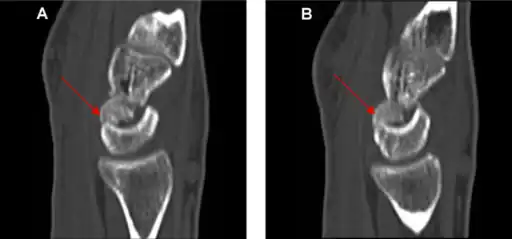

Diagnosis

Diagnosis is often by a posterior anterior wrist X-ray.[2]